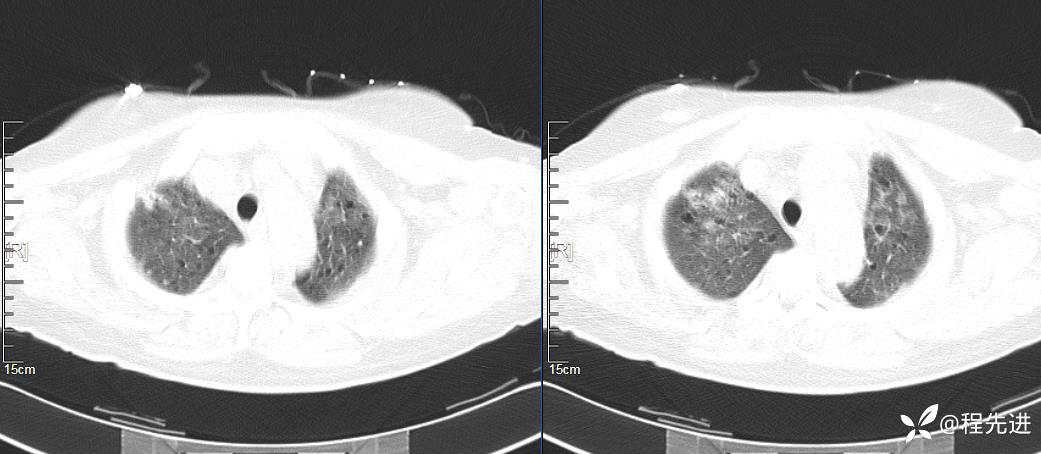

CT平扫(纵隔窗无特殊,就不上传了):

2、本例肺气囊分布有什么特点?肺气囊有无小叶核心?有没有间质纤维化及伴发结节?